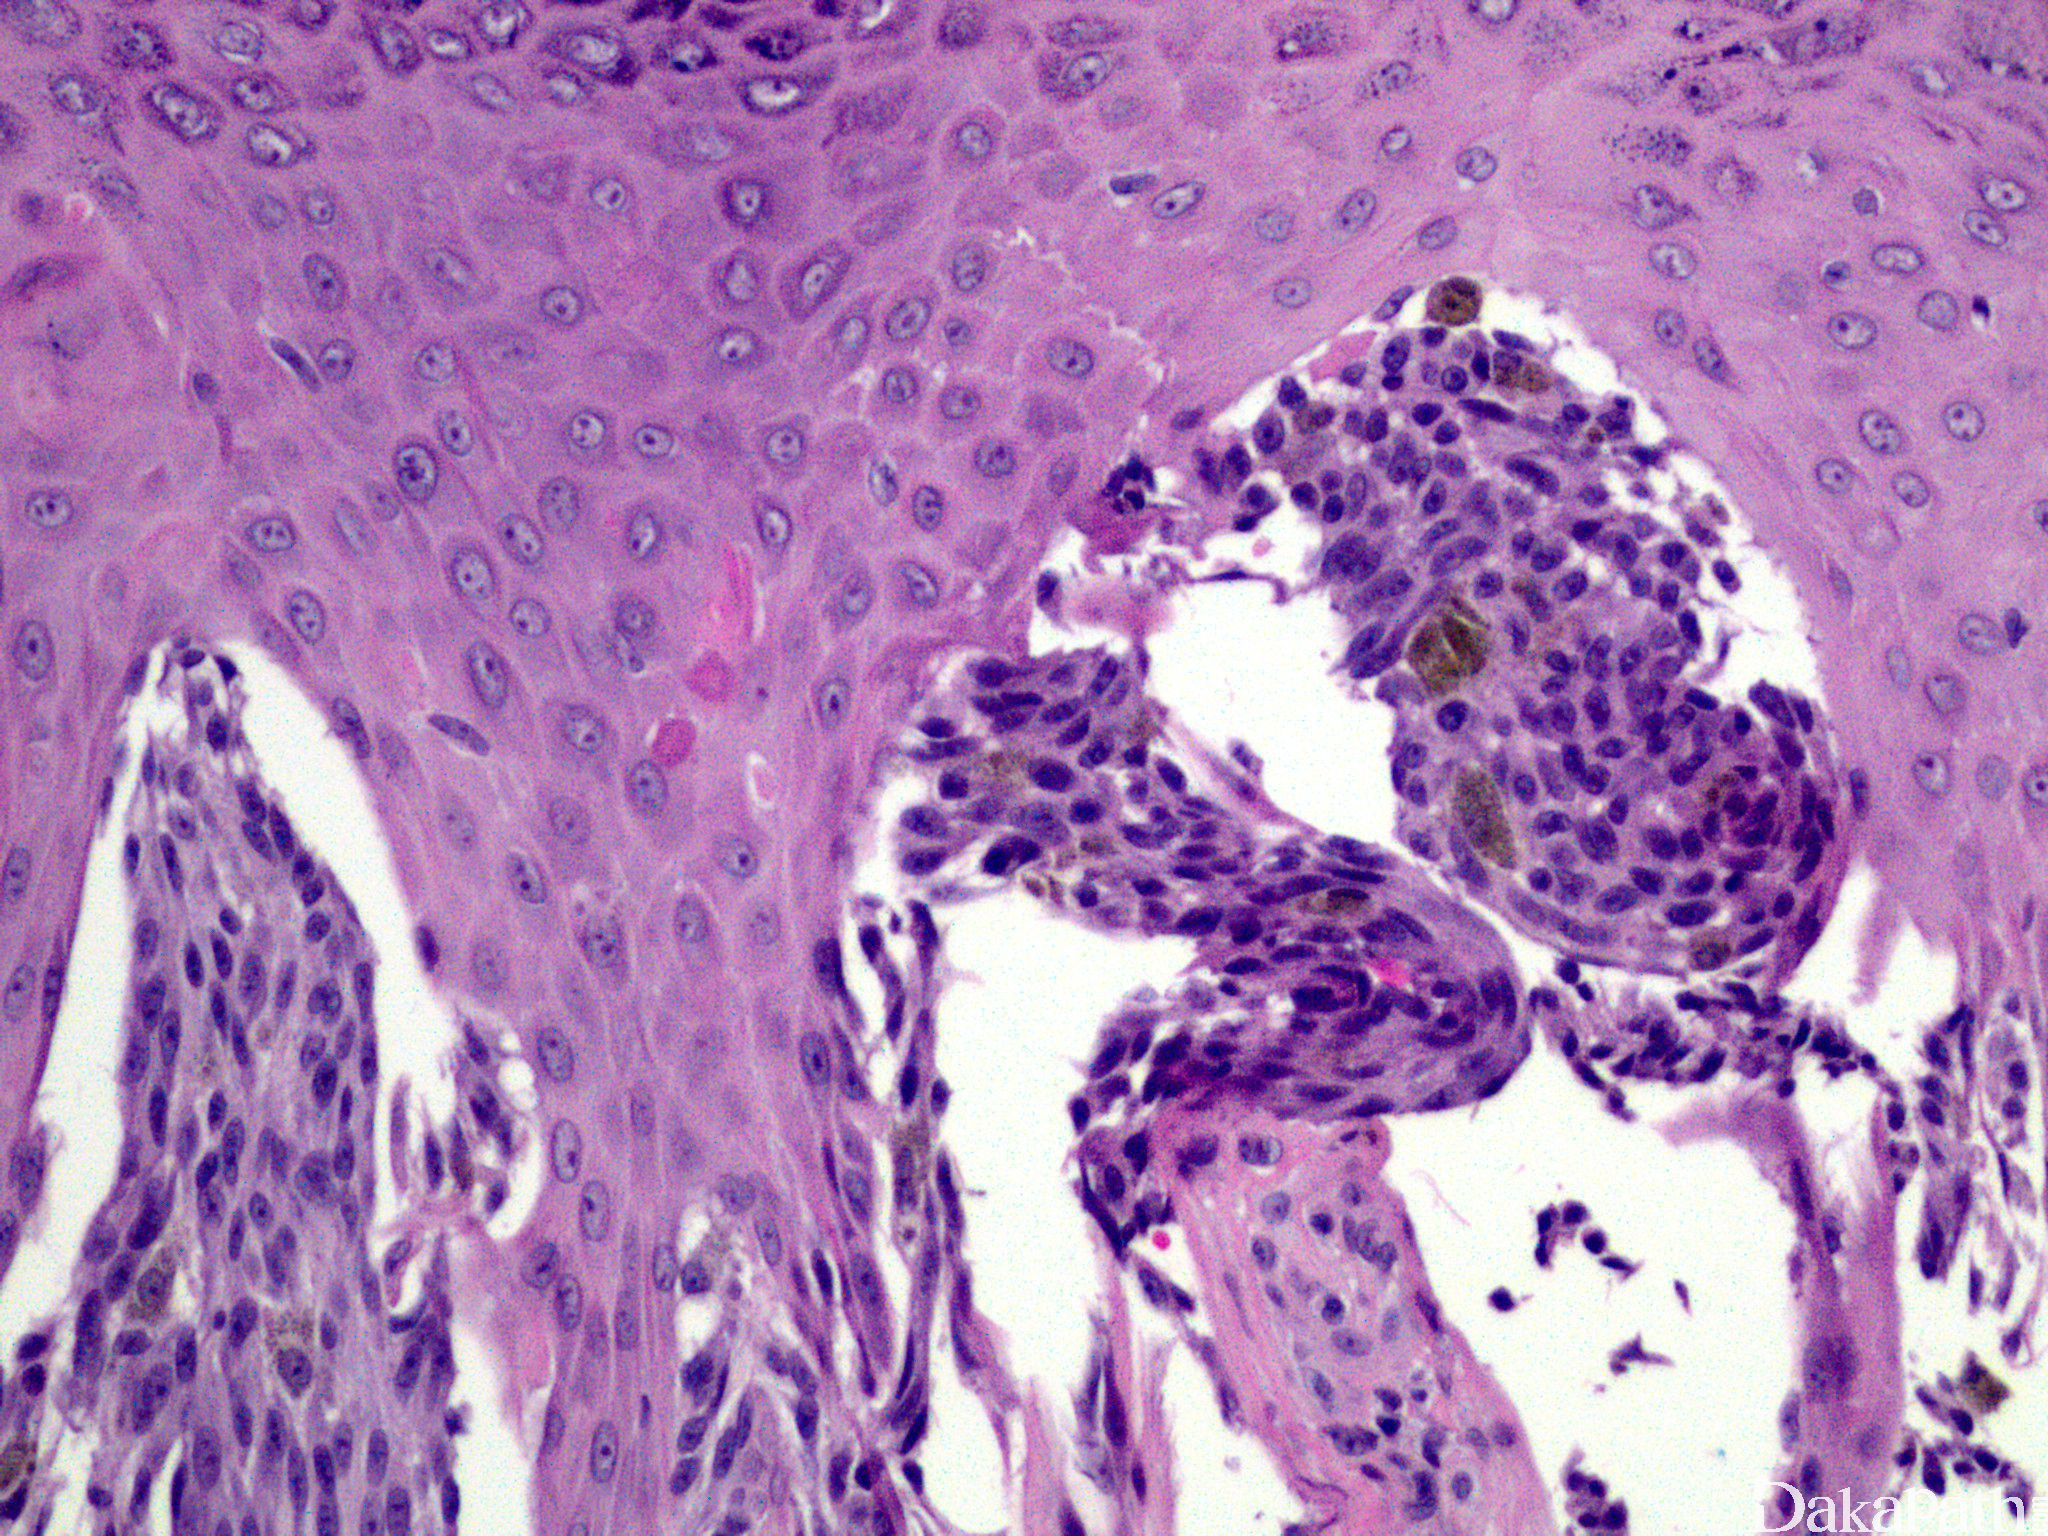

表皮增生、表皮-真皮交界处可见粉红色均质小球(Kamino 小体);

交界性或复合性 Spitz 痣部分病例梭形细胞呈紧密束状排列,与上皮脚平行,如悬挂的香蕉一样;交界处黑色素细胞巢常见“裂隙”;可见核分裂,但通常很少见并且局限在细胞密集病变的表浅部位;

主要由富于色素的细长梭形黑色素细胞组成,表皮-真皮交界处常有致密细胞巢,上皮脚常增生;

表皮各层角质形成细胞胞质常有色素颗粒;

常见暗淡的粉红色小球(Kamino 小体);

真皮浅层常见许多噬黑色素细胞。